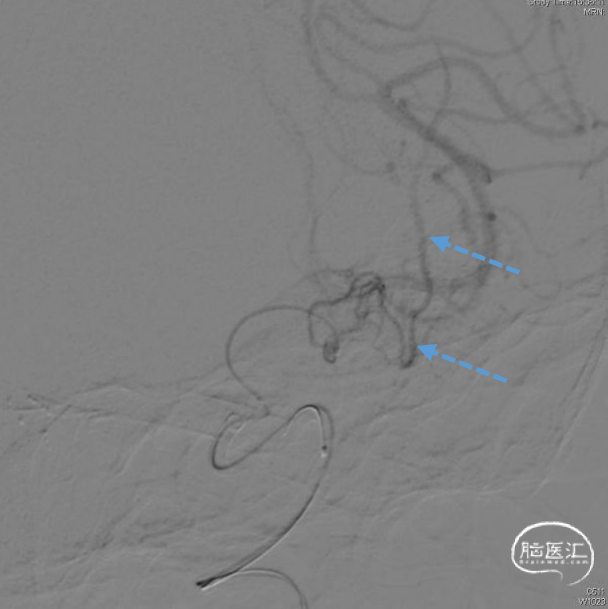

6F通桥银蛇DA远端通路导引导管到位后,工作角度微导管抵近造影,证实动脉瘤侧壁发出的边支向颞叶供血。

微导管送入弹簧圈 3mm×4cm,意向性栓塞。空出侧壁的边支动脉起始部。同时使用另一条微导管在远离边支的瘤颈部填(弹簧圈1mm×2cm)。

动脉瘤大部填塞后,边支动脉血流完好。